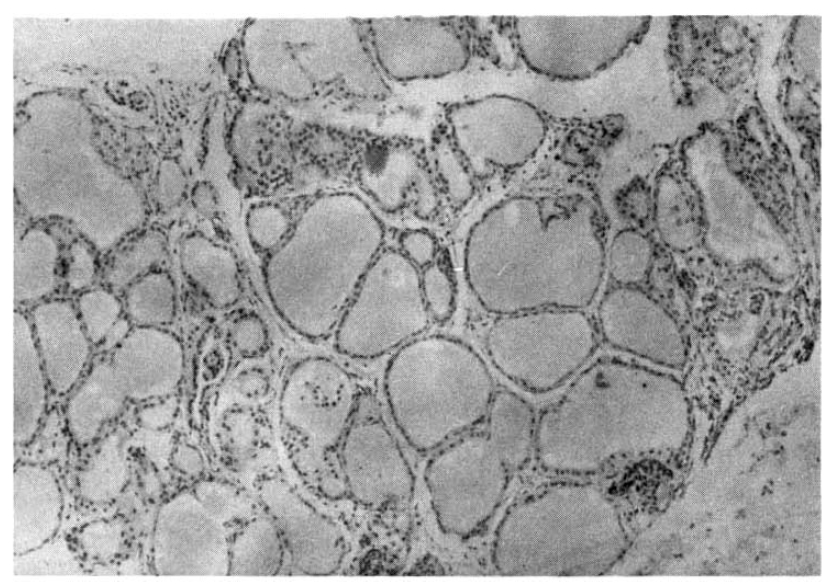

The 24 hour thyroidal radioiodine uptake was 56.5% and was not suppressed by T3 administration. At this time, TBII was 23.7 %, and TSAb 611 %, but TSBAb was persistently negative. Thyroid needle biopsy showed diffuse epithelial hyperplasia compatible with Graves’ disease (Fig. 1). Antithyroid medications were started and thyroid function normalized with a decrease in TBII and TSAb. TBII and TSAb disappeared ultimately and she remains euthyroid clinically and biochemically after withdrawal of the antithyroid drug until March 1988 (Fig. 2).

Fig. 1.

Thyroid needle biopsy performed when patient 1 became hyperthyroid shows diffuse epithelial hyperplasia compatible with Graves’ disease.